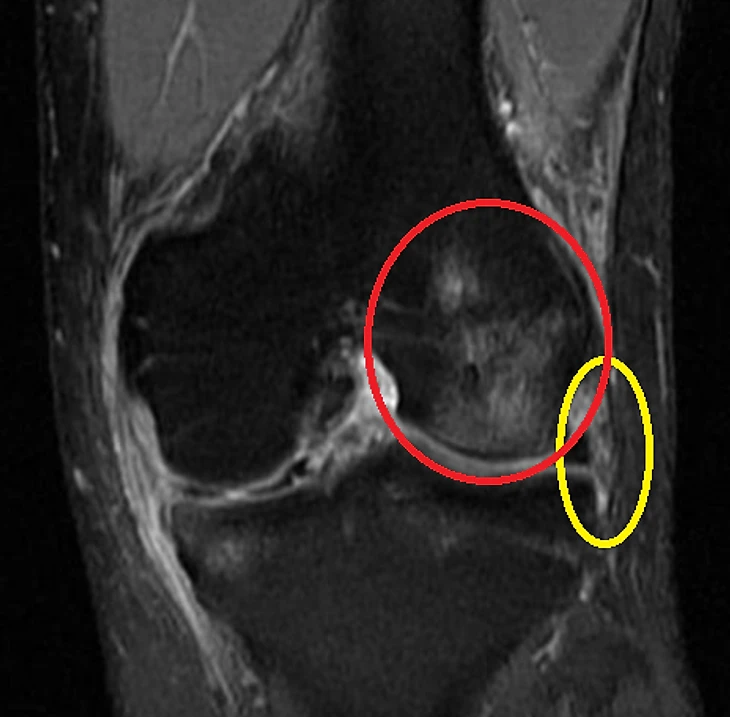

Там мы увидим примерно следующее: связка будет утолщена, но ее волокна остаются единым целым (желтый овал, сравните со здоровой связкой – на снимке слева). А в месте крепления связки может наблюдаться отек костной ткани (красный кружок, более светлый участок). В норме она однородного темного цвета. Это и есть контузия, которая возникла в момент удара – связка дернула тот участок кости, к которому крепится, спровоцировав такую реакцию. К счастью, связка осталась целой и не оторвалась от места крепления (тогда это был бы отрывной или авульсивный перелом).